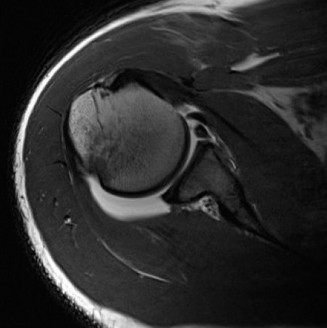

A 45-year-old carpenter presents with shoulder pain that has been ongoing for the last 3 months. He denies any significant injury. He describes night pain and significant discomfort at work. His imaging is shown in Figure 2–9. What is the most likely diagnosis?

🔍 Click to enlarge

🔍 Click to enlargeClinical Radiograph / Orthopedic Image

Figure 2–9_From Shi LL, Mullen MG, Freehill MT, et al. Accuracy of Long Head of the Biceps Subluxation as a Predictor for Subscapularis Tears. _Arthroscopy 2015;32(4):615–619.

Discussion

The correct answer is (A). Medial subluxation of the biceps tendon as seen in this MRI is commonly associated with a tear of the subscapularis tendon which attaches to the lesser tuberosity. This patient’s pain may in part be attributable to the subscapular tear and this should be evaluated for during physical examination. Supraspinatus tears (Answer B) cannot be easily visualized on axial views and are not associated with medial biceps subluxations. A labral tear and ALPSA lesion (Answers C and D) are not seen on the images provided. The question stem and MRI are not suggestive of shoulder instability (Answer E). Objectives: Did you learn...? Diagnose and treat acute rotator cuff tears?